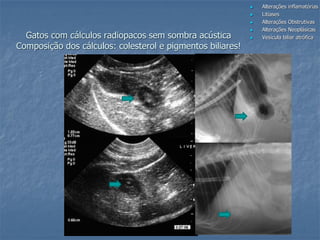

Gatos com cálculos radiopacos sem sombra acústica

Composição dos cálculos: colesterol e pigmentos biliares!